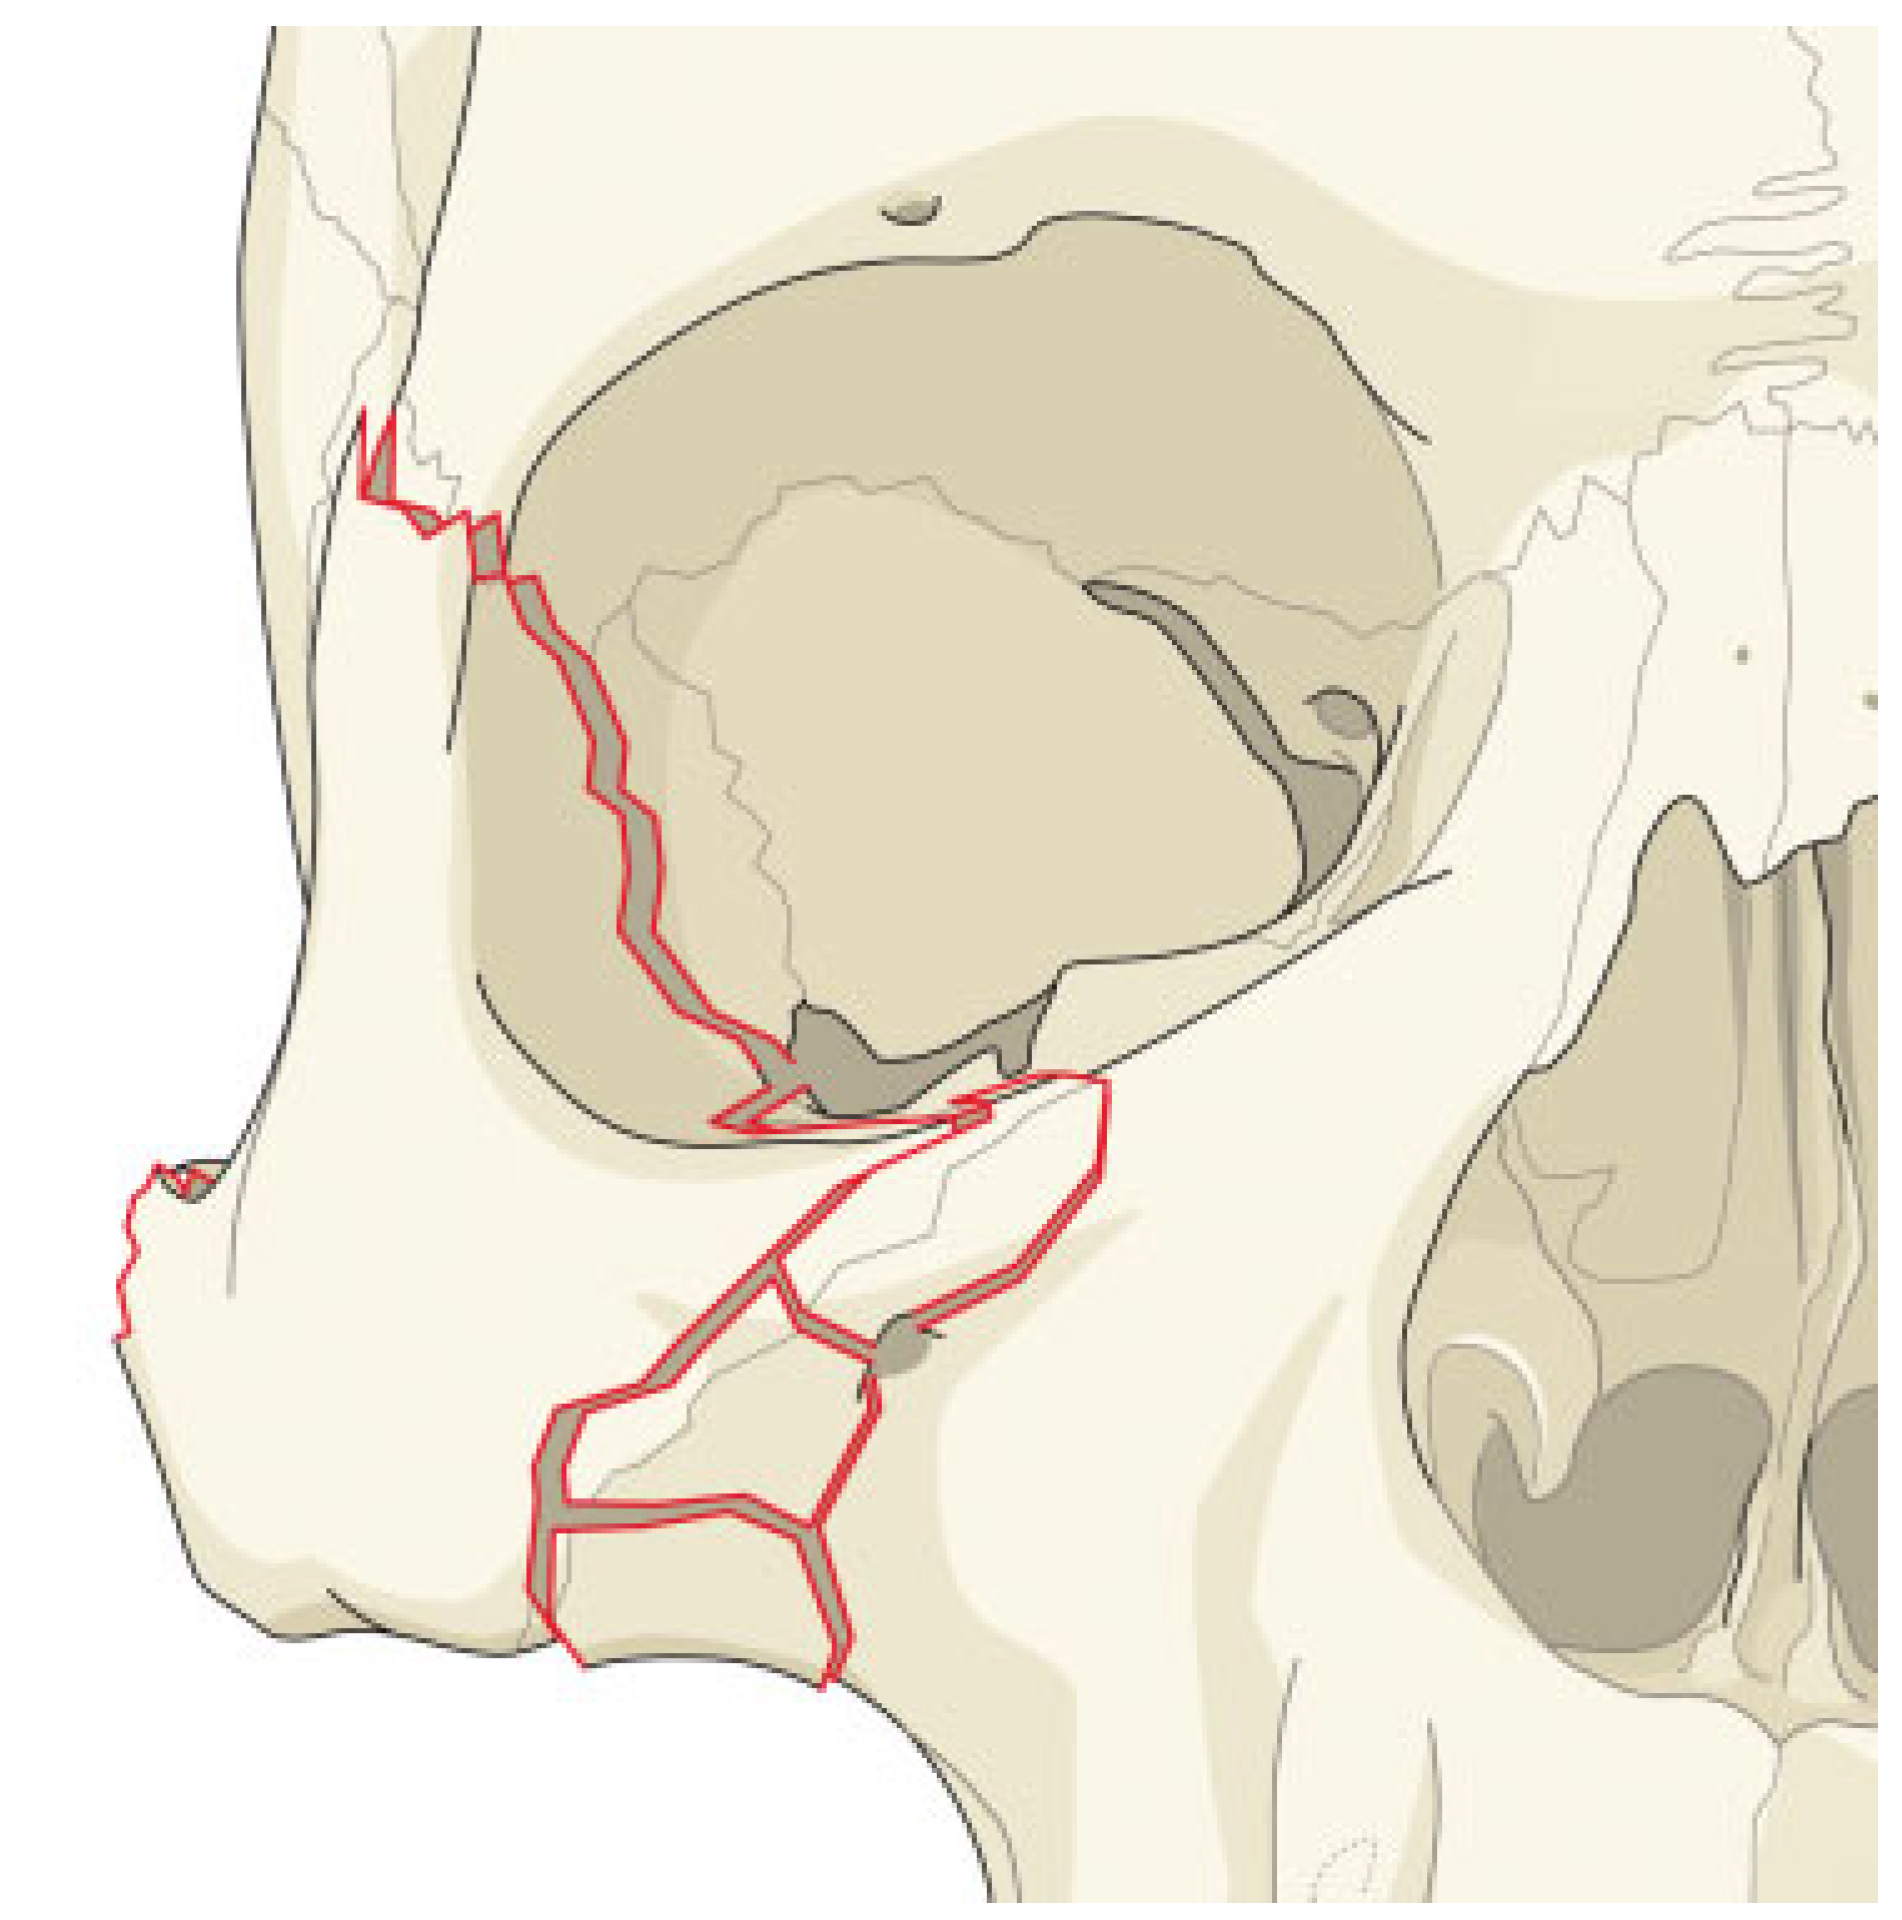

In cases where there is a simple fracture of the zygoma, and no comminution of the various zygomatic processes, the surgeon may be fairly certain of attaining a proper reduction of the zygoma without exploring the LOW (Figure 3). In cases where the zygomatic processes are comminuted, it will be much more difficult in assuring the three dimensional reduction of the zygoma and reduction will be less exact [6]. In these patients, dissection of the LOW, to confirm the proper alignment of the greater wing of the sphenoid and the zygoma, may be much more important (Figure 4).

Figure 4.

Comminuted fracture at the zygomatico processes with simple lateral orbital wall fracture.